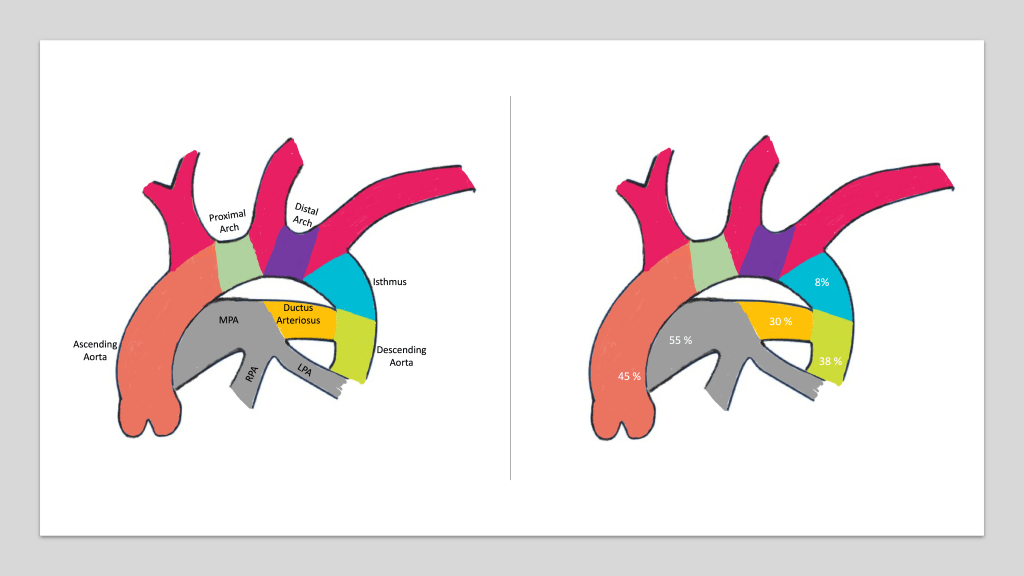

Pathophysiology of Fetal circulation in Coarctation of Aorta

In a fetus, the aortic isthmus receives approximately 8% of the combined ventricular output. If this flow decreases any further, the growth of the aortic isthmus and distal aortic arch get compromised. That can result in significant undergrowth and thus a narrowing of the isthmus.

As shown in the arch diagram, the aortic isthmus is a part of the aorta between the distal end of the origin of the left subclavian artery and the ductus. Isthmus narrowing occurs in approximately 90% of cases of coarctation of the aorta.